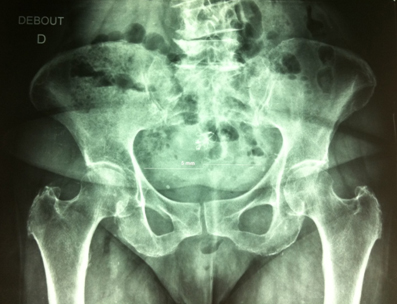

Mme F., 73 ans, est tombée en se levant la nuit.

Elle a ressenti une douleur vive aux fesses et a réussi difficilement à se relever. Elle a appelé sa fille pour aller aux urgences. La radiographie ne montrait pas de lésion osseuse mais des dégénérescences discales lombaires.